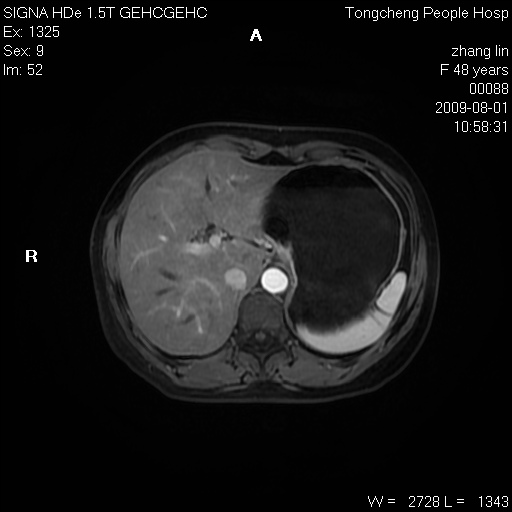

女,48岁。健康体检,彩超发现右肾占位性病变。平素健康。

临床诊断:右肾占位性病变,性质待定(囊肿?肿瘤?)。

上中腹部mr平扫+增强扫描,图像如下:

肝囊肿

慢性胆囊炎